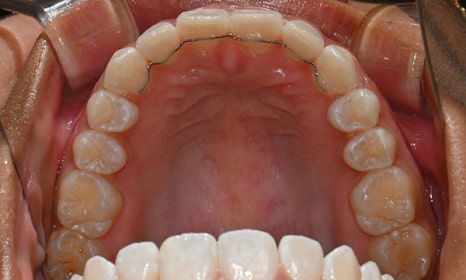

개포동 교정치과

교정 마무리 후 사진 (2025.8)

최종적으로 교정을 마무리한 후에는

위아래 치아 배열이 훨씬 가지런해졌고,

깊게 물렸던 과개교합도 크게 개선되었어요.

왼쪽 작은 어금니는 목표에서 제외했던 만큼,

아직 완벽하게 교합이 맞지는 않았지만,

치료 자료를 전달해 드리고 추후 본국으로 돌아가서

남은 치료를 이어서 받기로 하셨답니다.